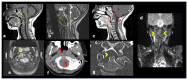

Mass lesions presenting at the craniocervical junction often present a unique challenge due to the complex anatomic arrangement limiting access for tissue diagnosis. The transoral approach has predominantly been used for percutaneous vertebroplasty of high cervical vertebrae with limited literature describing image guided biopsy for bony lesions in this region in the pediatric patient. We describe a technique of computed tomography guided transoral biopsy of a poorly differentiated chordoma located at the C1-C2 level in a 5-year-old child, and review this diagnosis.